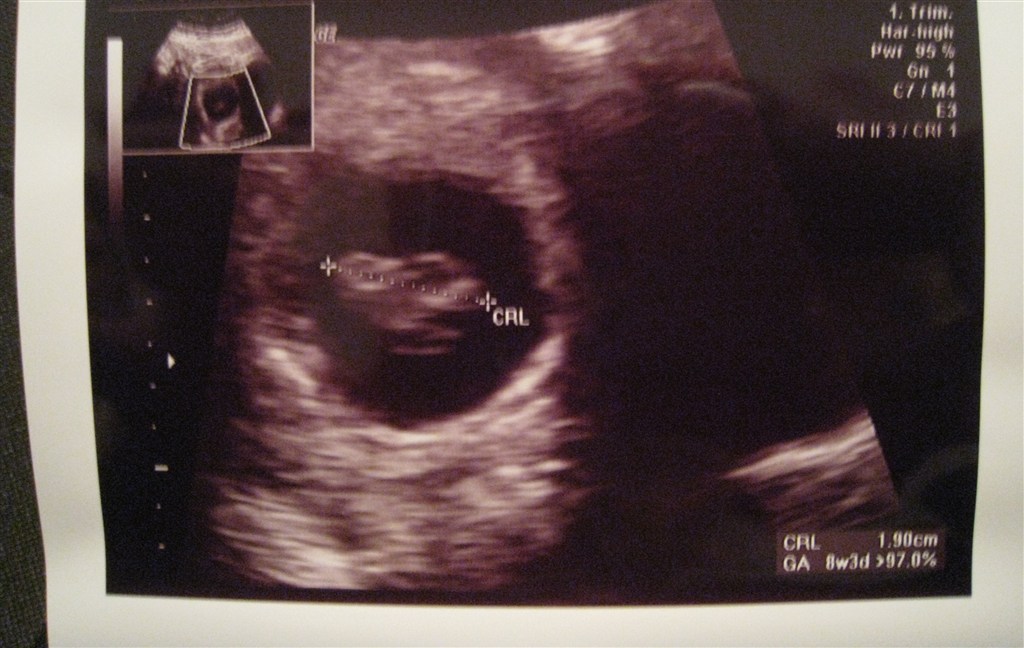

Ja sikke en nærmest uvirkelig forandring der er sket fra vores tidlig scanning i uge 8 og så frem til nu i uge 13.. Efter idag, må jeg simpelthen bare begynde at tro på det, sådan rigtig og for alvor..

Vi fik endda vist rigtig fine til risiko vurderingen - 14.398.. Weee!!!